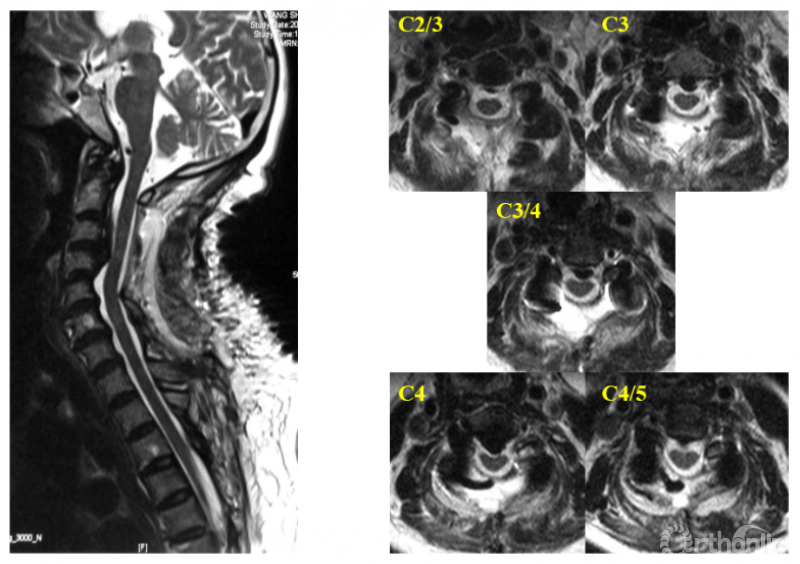

我们对57例患者的资料进行回顾,按减压节段分为C3-7组(n=32)和C2-7组(n=25)。测量并比较两组患者术后核磁上C2/3至C7/T1各节段脊髓前方至椎体后缘的距离(图4,在本研究中命名为脊髓前间隙,Anterior cord space, ACS),以了解不同的减压范围下减压效果的差异,以及将减压范围扩大至C2能带来的脊髓减压效果的获益究竟有多大。从而回答上述临床问题。

图4

本研究的结果提示,扩大减压范围至C2后,不仅使C2/3水平ACS增加,其相邻的C3/4水平ACS亦有明显增加,提高了C3/4水平避让前方压迫的能力(图5)。

图5

从数值上进行分析可以发现:C3-7组C3/4水平ACS均值6.60mm(95%CI:6.10~7.11),当该水平致压物中矢径>6.10mm时,C3-7减压即可能在C3/4水平残留压迫,当C3/4水平致压物中矢径>7.11mm时,C3-7减压则几乎不能充分解除压迫;如果扩大减压范围至C2,C3/4水平的ACS平均可达8.74mm(95%CI:8.10~9.38),最大可避让中矢径为9.38mm的前方致压物(图6)。

图6

此外,C4-5及以下节段未受C2减压的影响,提示当目标节段及其相邻节段的椎管充分扩大后,该目标节段即获得最大减压效应,而不会受到远隔节段是否减压的影响,亦即颈椎后路减压的效应主要受局部因素(局部硬膜囊膨起及局部曲度)的影响,这与系列一的研究结果是一致的。

最后,我们回到病例一,利用上述研究结果指导临床决策:C3/4水平致压物中矢径8.71mm>7.1mm,所以C3-7减压势必残留压迫,应选择C2-7减压,术后获得了9.34mm的ACS,充分解除了脊髓压迫(图7)。

图7